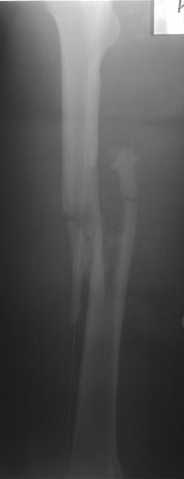

В приложении пример огнестрельного ранения бедра, оперированного на 2 сутки после ранения.

Штифтование было выполнено только на вторые сутки по причине задержки перевода из другого госпиталя, АБ профилактика была начата в другом учреждении, с момента госпитализации пациента к ним. Входное пулевое отверстие и зона введения штифта зажили первичным натяжением.

Единственно что наблюдал - замедленная консолидация, судя по серийным Рг граммам. В приведенном случае прии вялом мозолееобразовании сделал ошибку, решившись динамизировать гвоздь - перелом сросся со значительным укорочением бедра - повторная хирургия по удлинению бедра и проксимальным запиранием, больной мобилизован и вполне доволен(кстати заметить больной с ВИЧ инфекцией - изначально скомпрометированный иммунитет и несмотря на это, всё прошло без костной и мягкотканной инфекции.